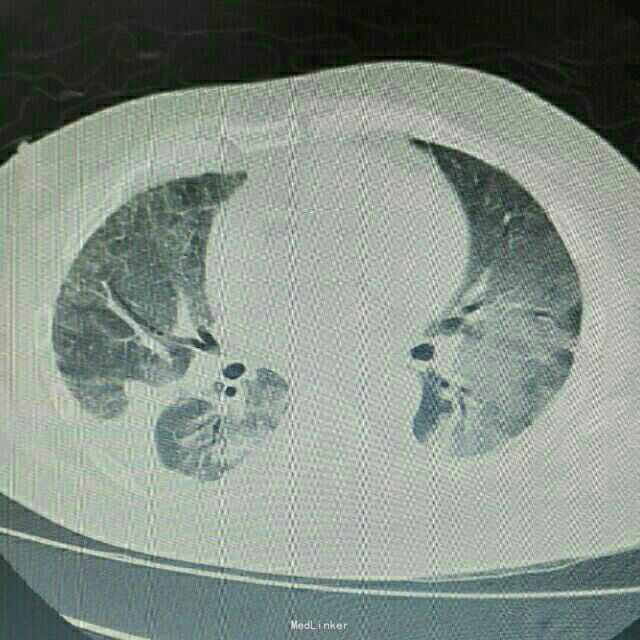

主诉:肾移植术后2月,发热、咳嗽5天 病史:患者男,45岁,因尿毒症于2月前在外院行异体肾移植术,手术过程顺利,术后恢复良好,移植肾功能稳定,服用FK506+MMF+Pred免疫抑制维持治疗。患者术后未规律门诊随诊,有情况变化时常电话联系行手术的医院,在术后免疫抑制剂服用剂量较大,为MMF1gBid+FK506 3.5mgBid+Pred25mgQd,其中FK506平时维持的浓度约10ng/ml。5天前开始出现发烧,最高体温38.8℃,自服“降温药”后体温可下降,伴咳嗽,无胸闷气促,无诉其他不适。

辅助检查:患者入院后症状进行性加重,入院2日后出现胸闷、气促,动脉血气分析提示氧分压为59mmHg,胸部CT提示双肺严重弥漫性炎症。

诊断:肺部感染;异体肾移植状态 治疗:患者入院后积极抗感染治疗,检查胸部CT和血气分析后给予吸氧等对症治疗,抗感染方案为泰能+伏立康唑+科赛斯+更昔洛韦,并停用所有口服免疫抑制剂,改为甲强龙40mgQd静脉滴注,患者治疗后肺部感染无明显好转,2日后转入ICU进一步治疗。